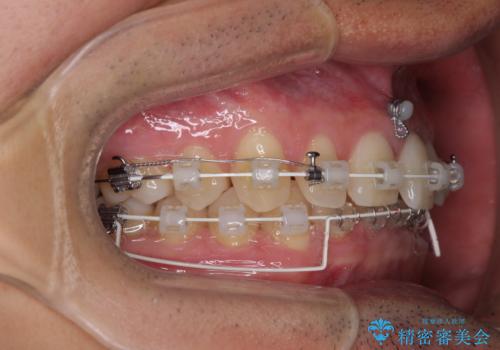

隙間の原因は、埋伏や前後に重なってしまっている上顎小臼歯と、下の前歯が見えなくなるくらいのディープバイトで、それらを改善する必要がありました。

アンカースクリューを用いて下に位置している上顎前歯を持ち上げるとともに、ワイヤー装置によりディープバイトの原因である奥歯の傾斜を改善することで、矯正治療を行っていくこととしました。

また、矯正治療に際し、4本全ての親知らずと、埋もれている右上小臼歯を事前に抜去することとしました。